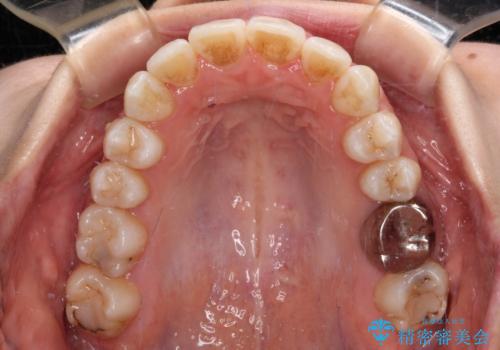

1. 【モニター】急速拡大装置 狭い歯列を拡大してワイヤー装置で短期間治療の治療前